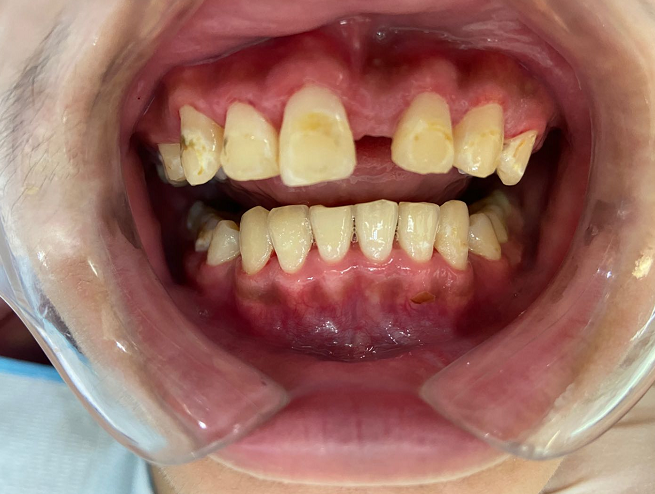

- 治疗后,患者已经恢复正常 -